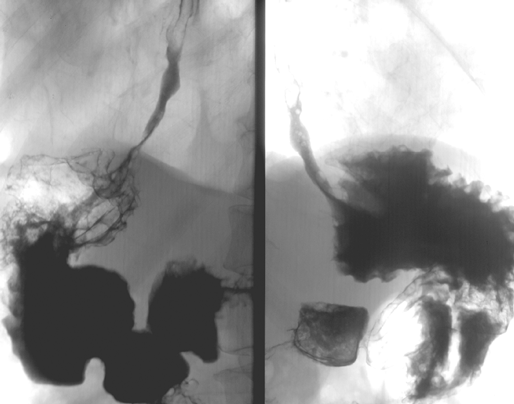

Рисунок 6. Выделена правая желудочная артерия (на лигатуре)

Рисунок 7. Лимфодиссекция зоны чревного ствола (выделены левая желудочная вена и левая желудочная артерия на протяжении)

Рисунок 8.Бурсосегментэктомия

Рисунок 9. Лимфодиссекция печеночно-двенадцатиперстной связки (видны воротная вена и общая печеночная артерия)

Рисунок 10. Окончательный вид послеоперационной раны после лимфодиссекции D2

Рисунок 11. Мобилизация панкреато-лиенального комплекса с лимфодиссекцией ворот селезенки

Рисунок 12. Окончательный вид панкреатолиенального комплекса после лимфодиссекции по ходу селезеночных артерии и вены в воротах селезенки

Рисунок 13. Трансхиатальная мобилизация пищевода с лимфодиссекцией заднего средостения

Рисунок 14. Окончательный вид раны после трансхиатальной резекции пищевода и формирования медиастинального пищеводно-кишечного анастомоза

Рисунок 15. Аорто-кавальная лимфодиссекция с визуализацией поясничной вены

Рисунок 16. Окончательный вид раны после забрюшинной парааортальной лимфодиссекции D3 (на лигатуре — левая почечная вена, на турникете — нижняя брыжеечная артерия)

Рисунок. 17. Мобилизация двенадцатиперстной кишки по Кохеру